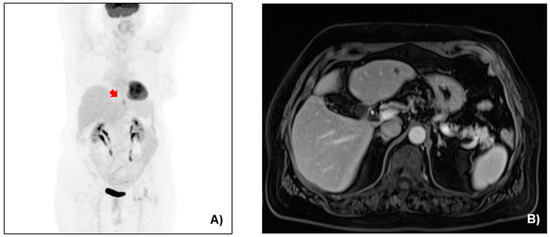

After the completion of a total of six cycles of chemotherapy, the re-staging CT showed major remission of the primary tumor and the metastatic sites (Figure 4). The imaging was complemented with FDG PET-CT and MRI-Liver (Figure 5). High SUV was noticed solely at the EGJ on the FDG PET-CT (Figure 5A). Out of the known hepatic lesions initially present, two were not visible on MRI and one had significantly reduced in size (from 2.6 to 0.7 cm) (Figure 5B). There was also major remission of the patient’s bulky lymph node packet at the lesser curvature. Gastroscopy findings following the completion of induction chemotherapy depicted a significant tumor remission with a single ulcer at the gastric cardia (Figure 6). Given the significant tumor response after induction chemotherapy, with the sole presence of residual active tumor exclusively at the EGJ together with the good performance status of the patient, a conversion surgical resection was recommended. Following MDT discussion, the patient was finally considered eligible for radical surgical resection, in which we decided to include surgical local management of all previous liver metastatic sites. The patient underwent an extended total gastrectomy with D2 lymph node dissection together with metastasectomy of the remaining liver metastatic lesions through an atypical left hepatectomy along with radiofrequency ablation (RFA) of a single scar tissue on the right liver, which was spotted at the site of previous hepatic metastasis and was evaluated using intraoperative liver ultrasound. Intraoperative images along with the image of the resected surgical specimen are shown in Figure 7.

Figure 5. (A) FDG PET-CT in coronal view, with high SUV noticed at the GEJ (red arrow). (B) Abdominal MRI in axial view, showing a scar lesion at the site of the largest hepatic lesion at the left liver lobe.